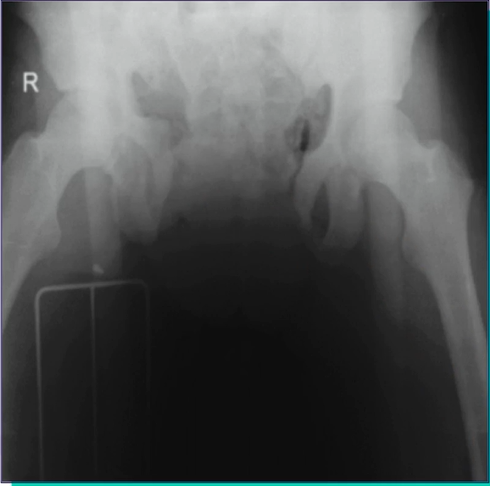

Q

O que se observa na imagem?

• Quais as estruturas comprometidas?

• É grave?

• Qual a conduta?

A

Trauma de pelve em livro aberto

• Ruptura do plexo venoso posterior e ramos arteriais da ilíaca interna

• HEMORRAGIA PODE SER FATAL

• Seguir fluxograma de trauma pélvico